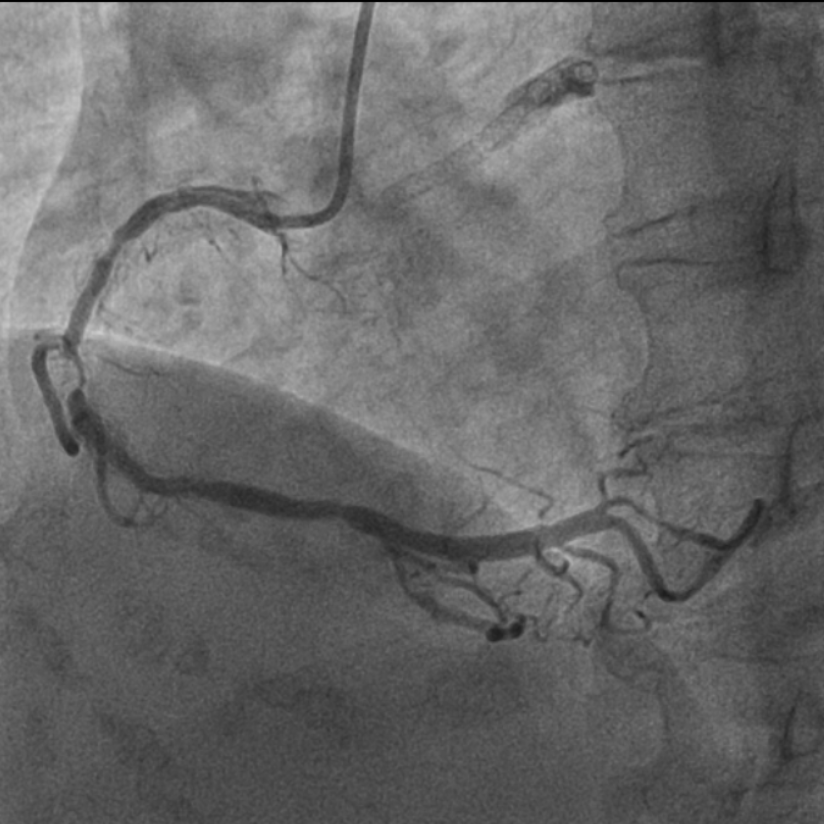

图2 术前造影提示多处再狭窄,冠脉钙化明显